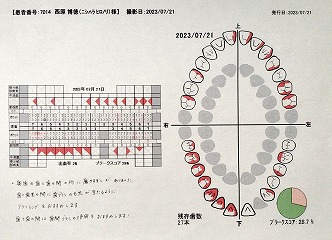

23.7.21 検査 PDF

23.10.27 検査 PDF

23.10.27 検査 PDF